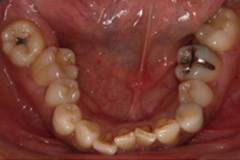

初診時の口腔内写真では左の咬合平面が下がっていました。

左上下顎臼歯部に著しい叢生があり、下顎臼歯部が大きく舌側へ傾斜していました。左はもちろん、右側も歯並びが崩れていて、右ではほとんど咬んでいなかったそうです。